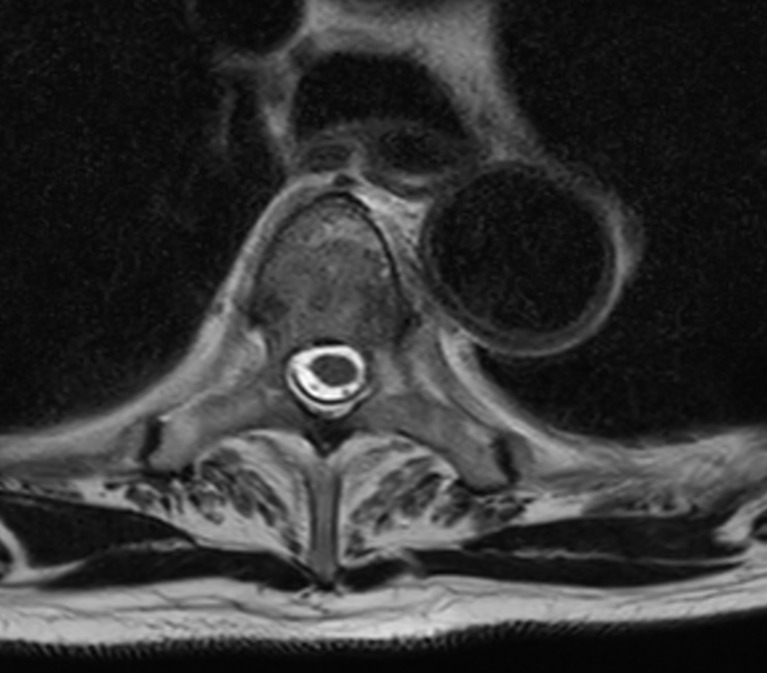

Axial T1w mDIXON XD TSE (Water only) +gado (T4)